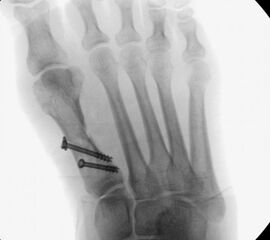

• Die Operationsplanung erfolgt anhand der Röntgenaufnahmen des Vorfußes unter Belastung in 2 Ebenen. Für die Verfahrenswahl sind wichtig der Intermetatarsalwinkel und die Breite des Os metatarsale, der Hallux valgus Winkel, der distalen Gelenkflächenwinkels (Distal Metatarsal Articular Angulation - DMAA), des Metatarsaleindex und Sesambeinposition (Abb. 1).

• Röntgenkontrollen (Vorfuß d.p. und seitlich) postoperativ ohne Belastung. Weitere Kontrollen erfolgen 6 Wochen, sowie 3, 6 und 12 Monate jeweils unter Belastung.